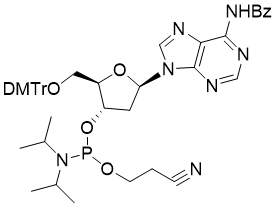

馬鞍山致研生物醫(yī)藥科技有限公司成立于馬鞍山市鄭浦港新區(qū)現(xiàn)代產(chǎn)業(yè)園。公司專(zhuān)注于生物小分子、醫(yī)藥中間體相關(guān)產(chǎn)品的研發(fā)和生產(chǎn),產(chǎn)品主要包括DNA亞磷酰胺單體、RNA亞磷酰胺單體、特殊單體以及按照客戶(hù)要求定制的RNA和DNA,并且公司提供定制合成等方面的研究服...

馬鞍山致研生物醫(yī)藥科技有限公司成立于馬鞍山市鄭浦港新區(qū)現(xiàn)代產(chǎn)業(yè)園。公司專(zhuān)注于生物小分子、醫(yī)藥中間體相關(guān)產(chǎn)品的研發(fā)和生產(chǎn),產(chǎn)品主要包括DNA亞磷酰胺單體、RNA亞磷酰胺單體、特殊單體以及按照客戶(hù)要求定制的RNA和DNA,并且公司提供定制合成等方面的研究服...